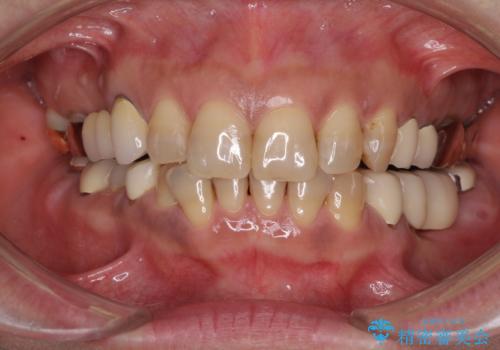

インプラントや歯周外科処置を用いた奥歯の補綴治療

- 下顎の左右奥歯が痛みがあり、噛めないとのことで来院された患者様です。

左右ともに歯根が破折しており、抜歯が必要であったため、抜歯後にインプラント補綴治療を行うこととしました。

左側は骨欠損が著しいことが予想されるため、骨造成術並びに歯肉移植術を併用することとしました。

仮歯がない状態を極力避けたいとのことで、外科処置を少しずつ進めていくことになり、治療期間は2年間を要しました。

治療後は痛みなどなく、快適に噛めるようになりました。